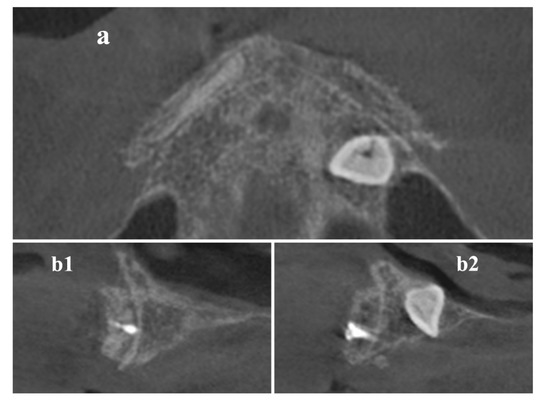

Preceding to the second phase, supplementary CBCT scans were performed to evaluate grafts gain (Figure 5).

Figure 5. CBCT scans were done after 9 months to define implant placement width and length, on (a) axial and (b1,b2) cross-sectional images.